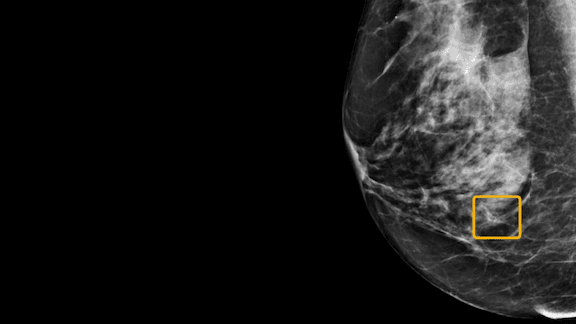

Breast cancer screening

Cancer in the Crosshairs: An AI model beat humans in diagnosing breast cancer from X-rays, but critics found the study lacking.

Computer vision has potential to spot cancer earlier and more accurately than human experts. A new system surpassed human accuracy in trials, but critics aren’t convinced.